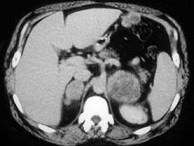

问题 男,56岁,有恶性黑色素瘤病史,请结合图像,作出诊断 ( )

选项 A、肾上腺转移瘤 B、肾上腺嗜铬细胞瘤 C、肾上腺髓样脂肪瘤 D、肾上腺癌 E、肾上腺腺瘤

答案 A